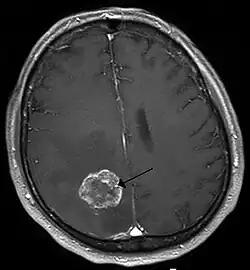

Positronen-Emissions-Tomographie

Die Positronen-Emissions-Tomographie (PET) als funktionelles bildgebendes Verfahren (sie gibt, vereinfacht gesprochen, die Stoffwechselaktivität bildlich wieder) erlaubt die Beantwortung spezieller Fragen. Eine solche wäre zum Beispiel die Unterscheidung eines lokalen Rezidivs von einer Strahlennekrose unter der Behandlung, wenn diese Differenzierung nicht aus der Kernspintomographie allein abgeleitet werden kann.[10]